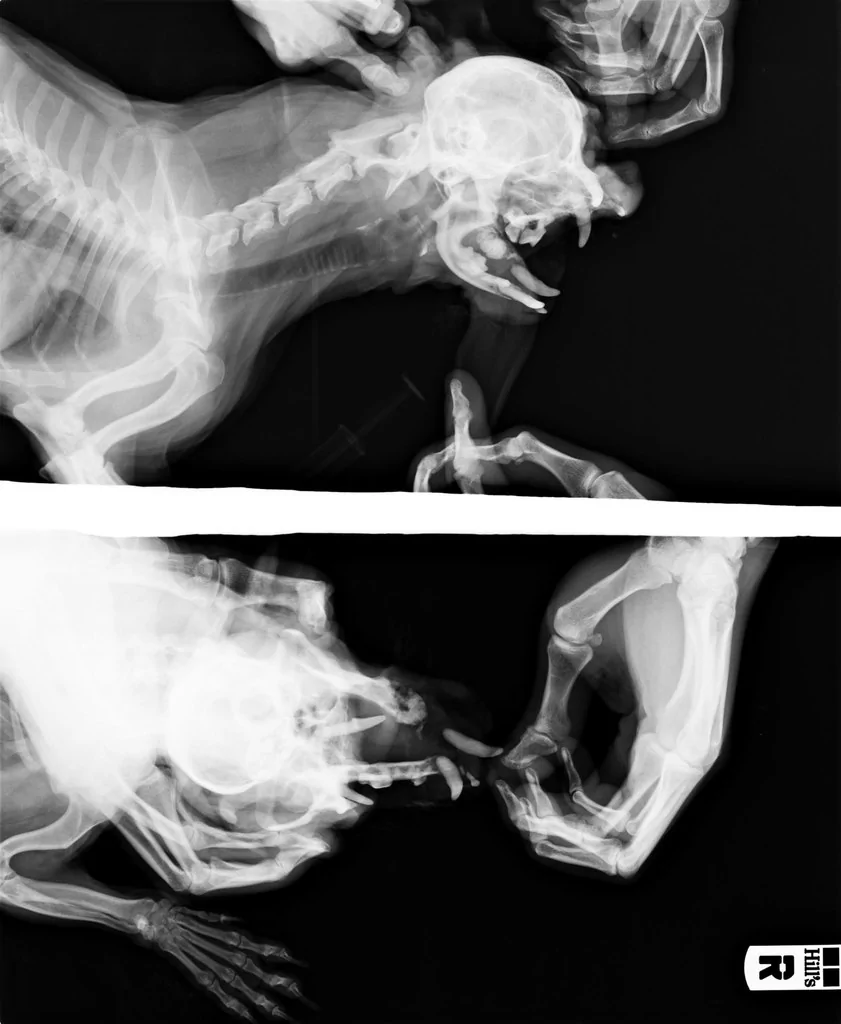

Рентгенологическая диагностика саркомы у кошек

Раздел: Визуальный дайджест